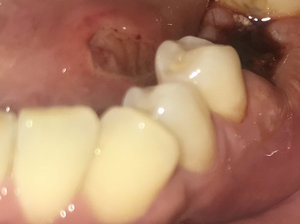

5 месяцев назад удалил зуб. И после этого начались проблемы со всей слизистой рта. Десна в месте удаления до сих пор красная и как бы немая. Так же вскорости после удаления на слизистой щек стали появляться как бы крупинки, спустя какое-то время они перешли по всей слизистой рта и увеличились в размере, так же по всей слизистой прощупывается при пальпации комки в подслизистом слое. Также начался зуд и жжение в языке и под ним. Анализ кандид не выявил.

Устал от бесконечных походов к врачам, но никто не может что-то определить. Может Вы сможете что-то посоветовать или назначить?

Я, как и все врачи, руководствуюсь осмотром и показаниями. Без осмотра и анализов сложно комментировать данный недуг. Если есть время (понимаю, что Вы устали от походов к врачу), то приезжайте, я сделаю все, что смогу.